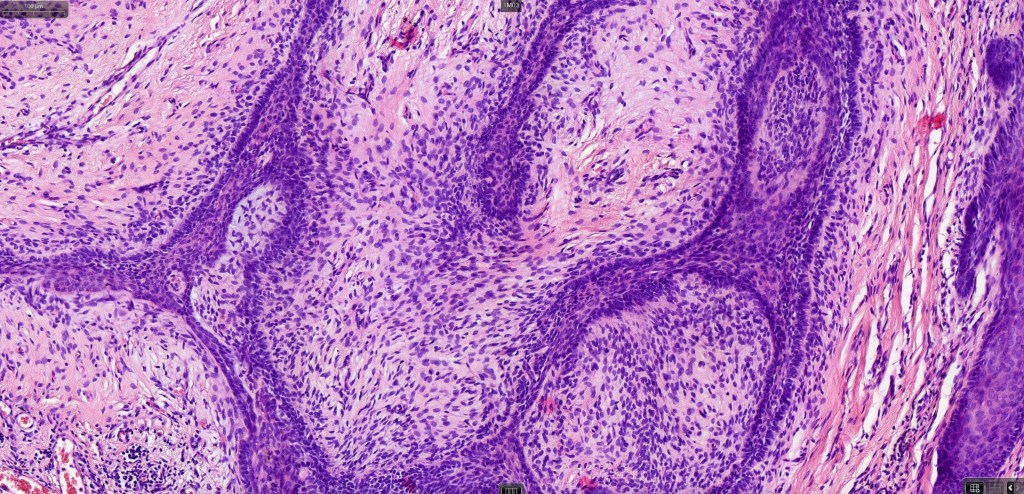

Histological features

•Multifocal origin from epidermis

•Anastomosing basaloid, narrow epithelial strands associated with a prominent fibrous (sometimes myxoid) stroma

•Peripheral palisade

•Round to oval vesicular nuclei with small nucleoli

•Mitoses very scanty or absent

•Retraction artifact variably present